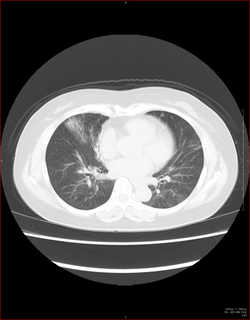

CTで見ると…